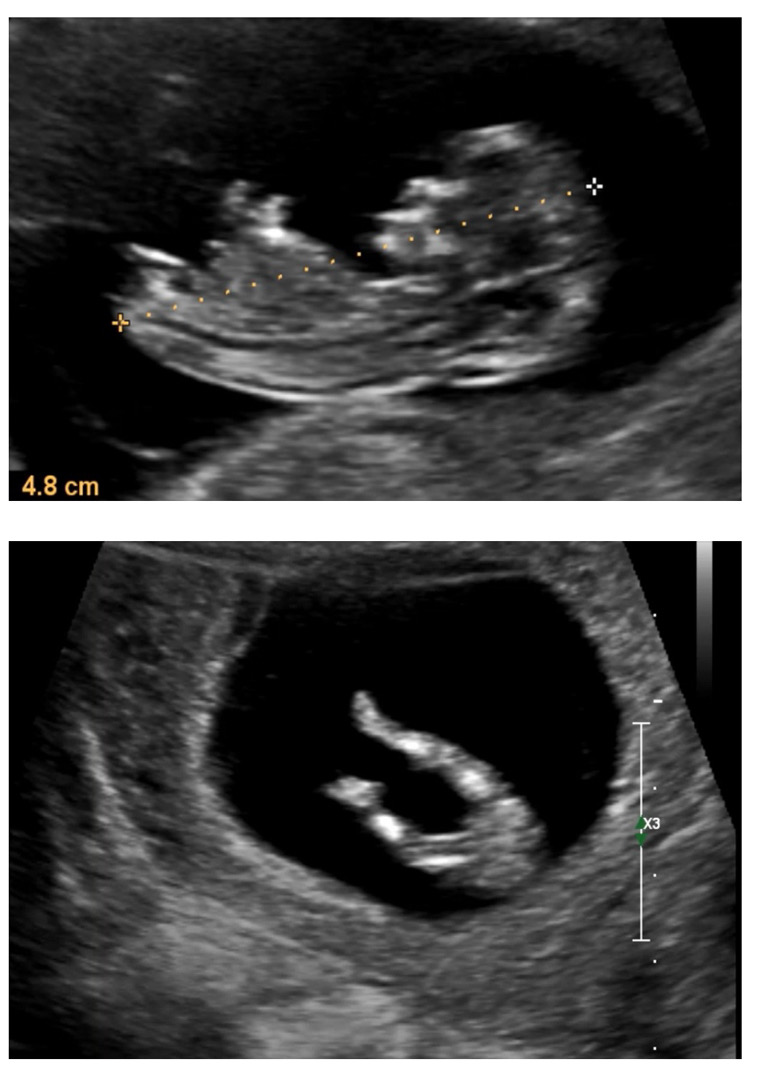

11주 2일차에요

성별 알 수 있을까요..? ㅎㅎㅎ 아직 이르지만 궁금해요